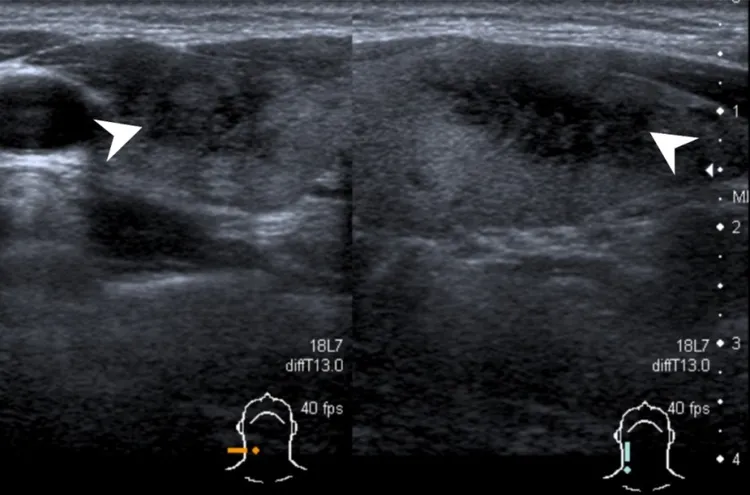

萬芳醫院新陳代謝科醫師劉漢文說明,亞急性甲狀腺炎是甲狀腺組織的發炎反應,因為可能與病毒感染有關,也稱為病毒性甲狀腺炎,好發於30~50歲女性,其病狀為甲狀腺腫大、壓痛,疼痛感可能蔓延至喉嚨、下巴、耳朵,偶爾會伴隨發燒,而處在不同的發炎時期,也會出現甲狀腺亢進或低下的症狀。

亞急性甲狀腺炎和上呼吸道感染的病毒有關,劉漢文指出,在確診前的1~4週裡,病人會出現發燒、疲勞、全身痠痛、咳嗽流鼻水、脖子疼痛等類似普通感冒的症狀,因而容易被忽略,雖說大部分情況能夠自癒,但病程往往長達數月,若沒有保持追蹤,恐進展成永久性甲狀腺功能低下而沒有發現。